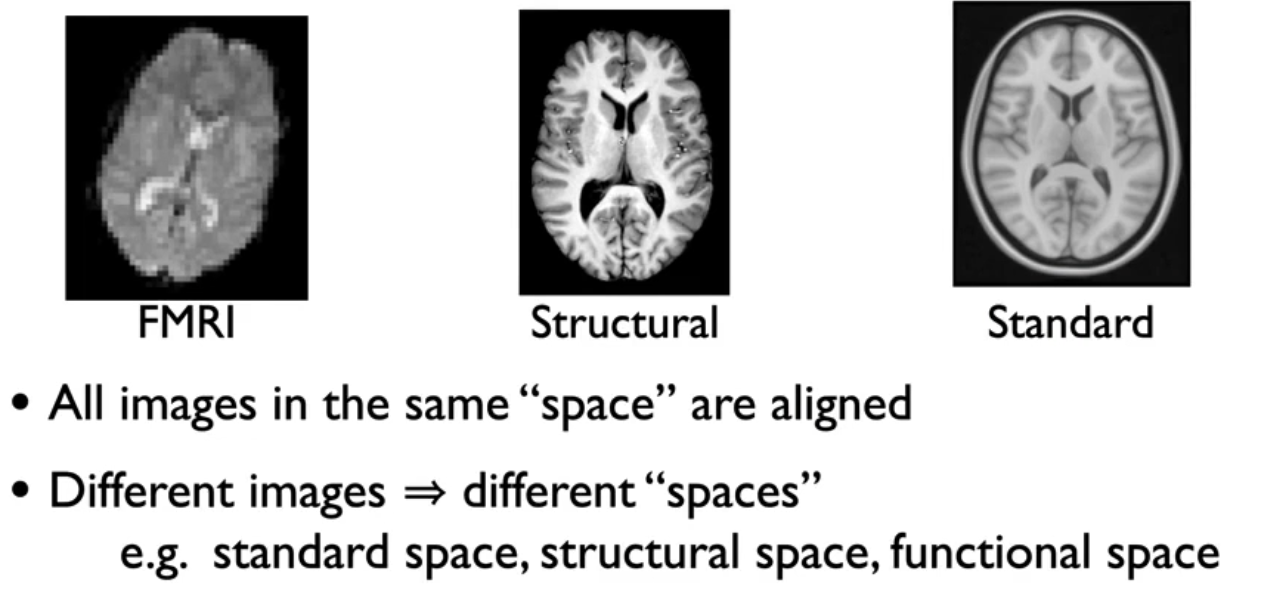

image space

图像空间包含3种:标准空间,结构空间,功能空间

每个空间又可以有不同的分辨率,比如标准空间模板MNI152,就有1mm,2mm,0.5mm的分辨率。

图像从一个空间到另一个空间的转换就叫空间变换。